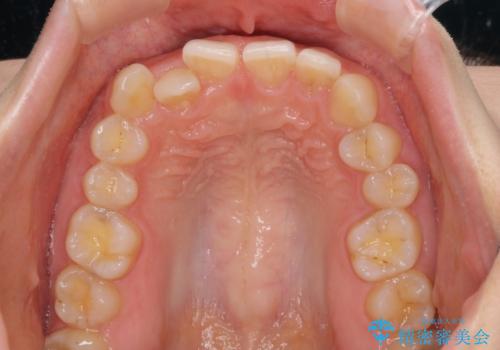

- 前歯の隙間やクロスバイトを気にして来院された患者様です。

結婚式の予定があり、可能であれば結婚式までに治療を終えたいとのことで、短期間で治療をおける可能性の高いワイヤー装置にて矯正治療を行うこととしました。

ギリギリとなりましたが、結婚式直前にワイヤー装置を外すことができました。

ワイヤー装置除去後に細かい部分を短期間のマウスピース矯正にて仕上げました。